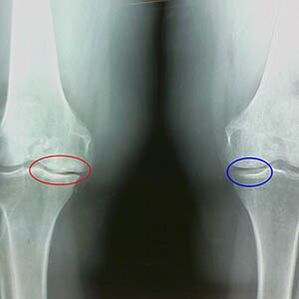

The determination of the degree of osteoarthritis occurs by X -raysrevealing participation in the pathological process of bone structures.Its change indicates that the muscle system has been in an imbalance for 5-10 years.As a rule, peopleDolores Dolores experience for several years.

The second stage of osteoarthritis is considered easy.The radiography reveals significant bone spuries, but the cartilage is not affected.The amount of synovial fluid is reduced, but the symptoms of pain appear after a long walk and race, stiffness in the joint and pain when folding and in the knees position.

Initial characteristics of X -Ray of the second stage of the osteoarthritis of the knee:

- the pointed edges of the interceptive tubers in the tibia, where the ligament is joined in the form of a cross;

- narrowing of the articular gap on the medial side;

- The pointed edges of the condiles of the bones on the medial sides, less frequently on the side, depending on the development of the valgo or the deformation of the diverse joint.

For the second stage in LarsenThe narrowing of the articular gap in more than 50% is characteristic, but this can only be verified in dynamics or comparison with a different joint.

Radiography shows the presence of osteophytes, a change in space between femoral and warm bones, indicating the loss of cartilage in the knee.Sometimes, the x line of the knee joints shows significant cartilage wear signs, but patients do not experience significant pain.On the contrary, the osteoarthritis of the first stage can interrupt the knee function, since the cause of pain is hypotonic muscles.